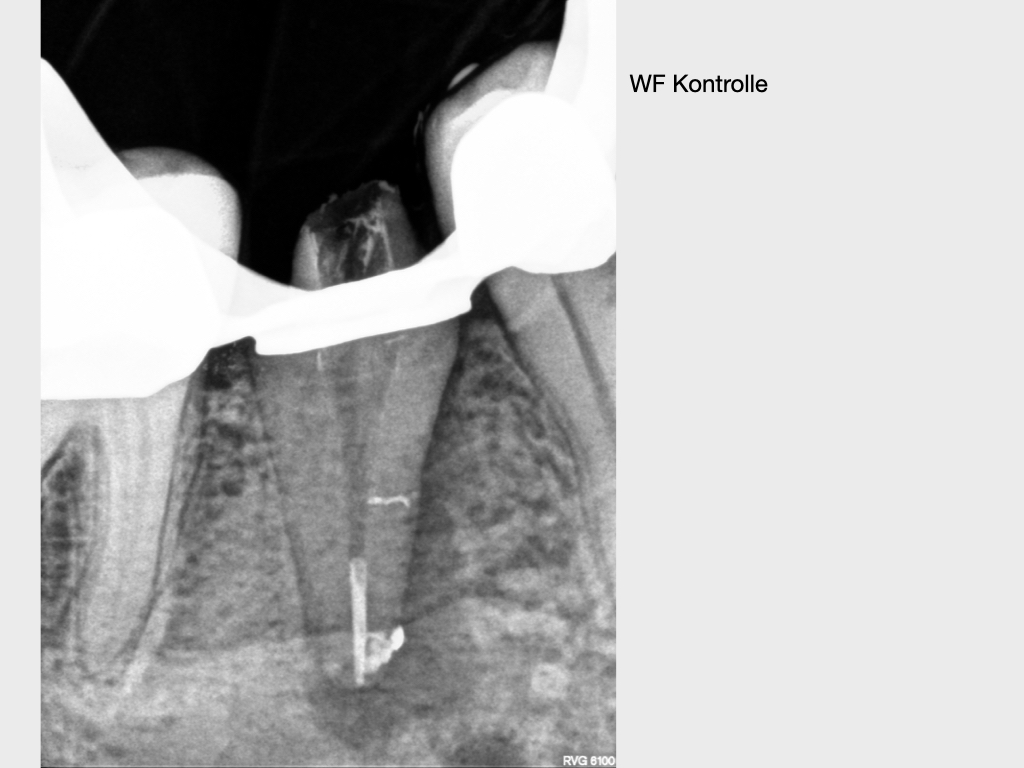

lateraler Kanal.016

Lateraler Kanal